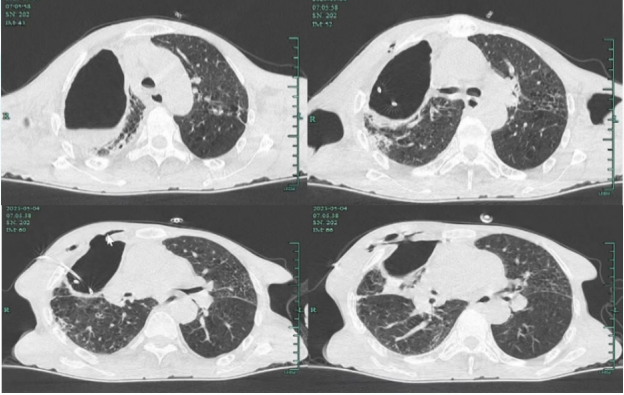

• 胸部CT右侧肺癌术后,右上包裹性液气胸引流术后改变,胸膜瘘;肺气肿,两肺散在炎性病变,部分间质性改变,合并多处支气管轻度扩张。脓腔范围较前增大,右侧胸壁支撑有断裂置入引流管(图2)

图片

2 患者入院胸部CT(2023-05-04)